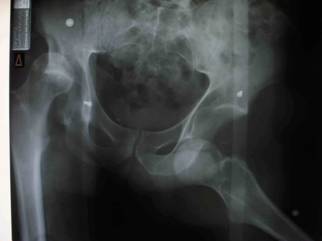

The patient had no other neurologic deficiency. Plain

radiographs reveal an anterior dislocation in the left hip and

posterior dislocation in the right hip associated with posterior

wall fracture. There was also and a bone fragment in the right

acetabular cavity. (Fig 1)At the emergency room and under

Fig.1: AP radiograph of the pelvis at presentation

showing anterior dislocation of the left hip and posterior

dislocation with associated posterior wall fracture in the right

hip.